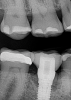

A 56-year-old woman was referred for the treatment of a dental implant at the site of the maxillary right canine, No. 6, which was diagnosed with moderate peri-implantitis subcategory A (Figure 1).19 The implant had been placed 3 years prior and had healed uneventfully, but at a recent maintenance visit purulence and pocket depth of up to 8 mm were noted. The patient's medical history included hypothyroidism, for which she took levothyroxine, and an allergy to sulfa medications. She had a high smile line, and the dental implant was 3 mm wide with an anodized surface.

Fig 1. Pretreatment radiograph of the implant, maxillary right canine site. Bone loss was suggested at the mesial and distal aspects. v

Figure 1